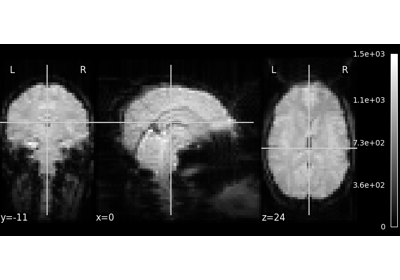

Let’s have a look at this image:

nilearn.plotting.plot_img(nilearn.datasets.MNI152_FILE_PATH)